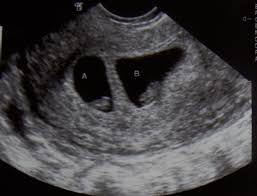

12. Twin Pregnancy

i.

DCDA – dichorionic diamniotic

– dua placenta dua karung

Kembar tidak seiras dan boleh

berlainan jantina.

ii.

MCDA – Monochorionic

diamniotic – Satu placenta dua karung

Kembar seiras, sama jantina

iii.

MCMA (MOMO) –

Monochorionic monoamniotic – Satu placenta, satu karung

Kembar seiras, sama jantina dan boleh

menjadi kembar siam.

septated

membrane

Lamda Sign